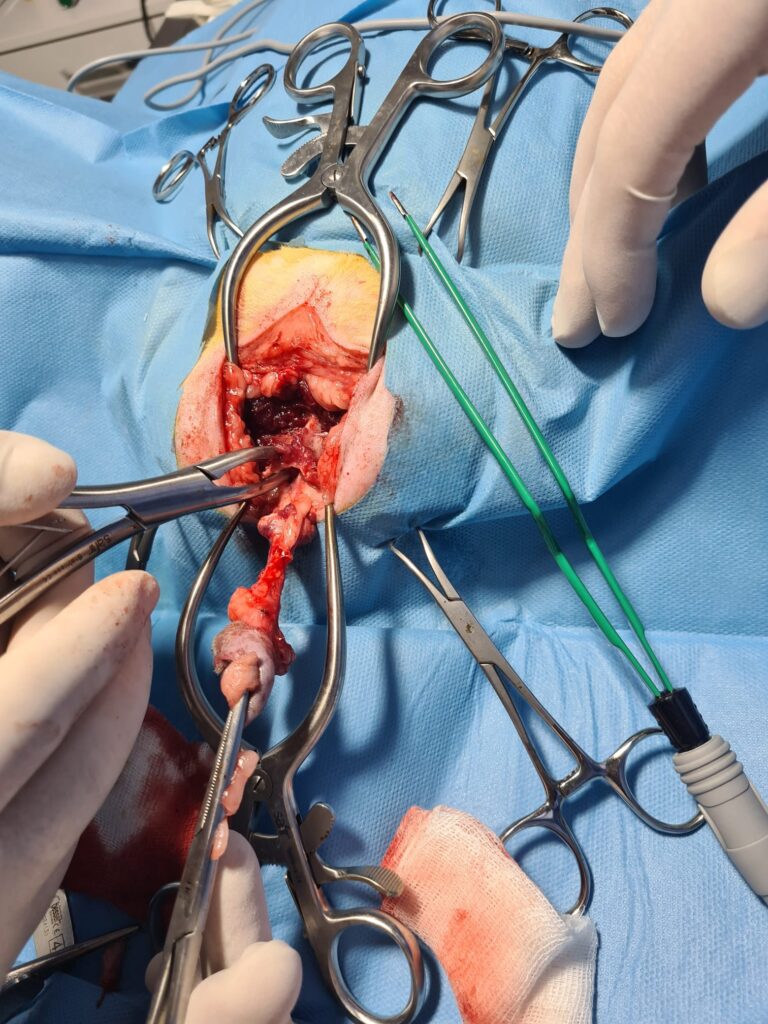

3. Cerrahi Müdahale

Kronik veya tekrar eden tıkanıklık durumlarında, Perineal Üretrostomi (PU) adı verilen cerrahi bir işlem gerekebilir. Bu ameliyat, idrar yolunun genişletilmesini içerir ve tıkanıklık riskini büyük ölçüde azaltır.